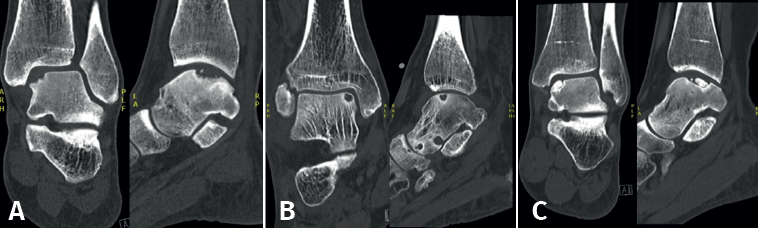

Las técnicas de fijación han demostrado éxito clínico y radiológico en 8 de cada 10 pacientes y el éxito también se ha mantenido a largo plazo (Figuras 5 y 6). Dado que estas técnicas preservan el cartílago hialino y proporcionan una cicatrización superior del hueso subcondral, resultan ventajosas frente a otras opciones de tratamiento quirúrgico de las OLT, cuando son factibles(39,41).

Figura 5. Tomografía computarizada preoperatoria (A y B) y postoperatoria al año (C y D) de un paciente tras la fijación.